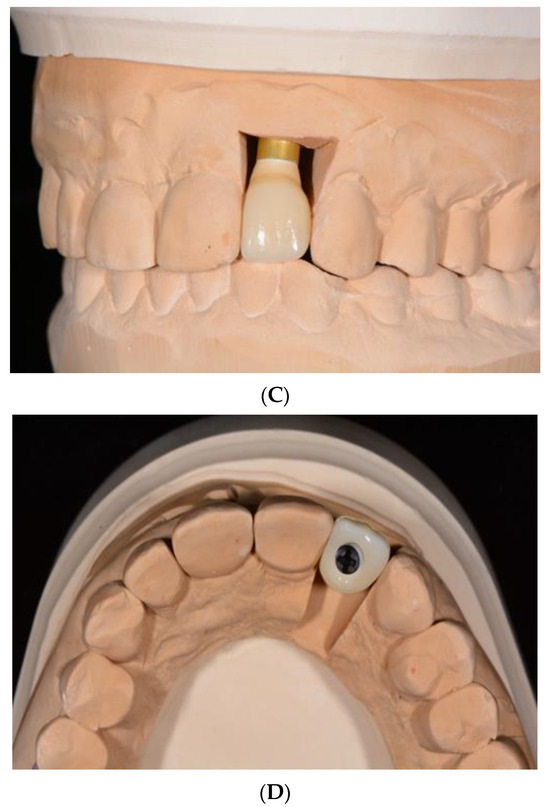

- Pirker, W.; Kocher, A. Immediate, non-submerged, root-analogue zirconia implant in single tooth replacement. Int. J. Oral Maxillofac. Surg. 2008, 37, 293–295. [Google Scholar] [CrossRef]

- Pirker, W.; Kocher, A. Immediate, non-submerged, root-analogue zirconia implants placed into single-rooted extraction sockets: 2-year follow-up of a clinical study. Int. J. Oral Maxillofac. Surg. 2009, 38, 1127–1132. [Google Scholar] [CrossRef]

- Pessanha-Andrade, M.; Sordi, M.B.; Henriques, B.; Silva, F.S.; Teughels, W.; Souza, J.C.M. Custom-made root-analogue zirconia implants: A scoping review on mechanical and biological benefits. J. Biomed. Mater. Res. B Appl. Biomater. 2018, 106, 2888–2900. [Google Scholar] [CrossRef]

- Pirker, W.; Wiedemann, D.; Lidauer, A.; Kocher, A.A. Immediate, single stage, truly anatomic zirconia implant in lower molar replacement: A case report with 2.5 years follow-up. Int. J. Oral Maxillofac. Surg. 2011, 40, 212–216. [Google Scholar] [CrossRef]

- Van Dooren, E.; Calamita, M.; Calgaro, M.; Coachman, C.; Ferencz, J.L.; Pinho, C.; Silva, N.R. Mechanical, biological and clinical aspects of zirconia implants. Eur. J. Esthet. Dent. 2012, 7, 396–417. [Google Scholar] [PubMed]

- Regish, K.M.; Sharma, D.; Prithviraj, D.R. An overview of immediate root analogue zirconia implants. J. Oral Implantol. 2013, 39, 225–233. [Google Scholar] [CrossRef] [PubMed]